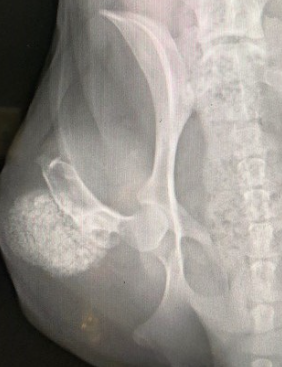

방사선 검사를 해보면 석회화 된 대형의 종괴가 특징이라고 할 수 있다.